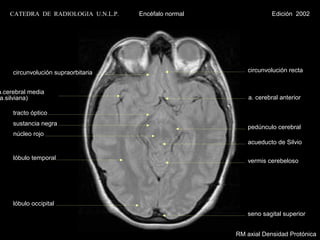

CATEDRA DE RADIOLOGIA U.N.L.P.   Encéfalo normal                Edición 2002

circunvolución supraorbitaria                        circunvolución recta

a.cerebral media

a.silviana)                                               a. cerebral anterior

tracto óptico

sustancia negra

pedúnculo cerebral

núcleo rojo

acueducto de Silvio

lóbulo temporal                                      vermis cerebeloso

lóbulo occipital

seno sagital superior

RM axial Densidad Protónica